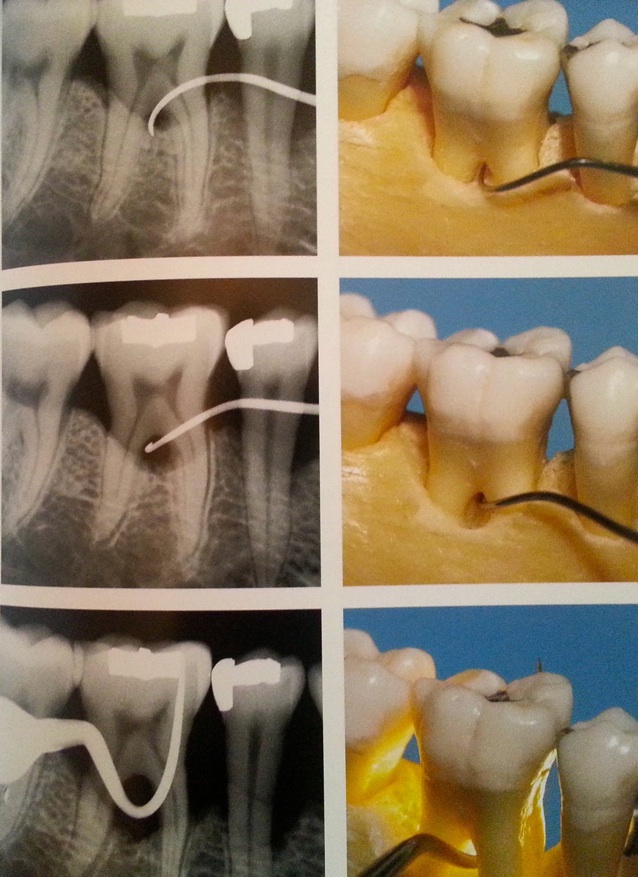

En fonction de la profondeur des poches parodontales on décide du type de traitement :

1.moins de 5 mm = non chirurgical ( détartrages et surfaçages radiculaires )

2.plus de 5 mm = chirurgical

L’atteinte de la furcation interradiculaire est un facteur aggravant.

Résorption osseuse interradiculaire, classification des furcations: